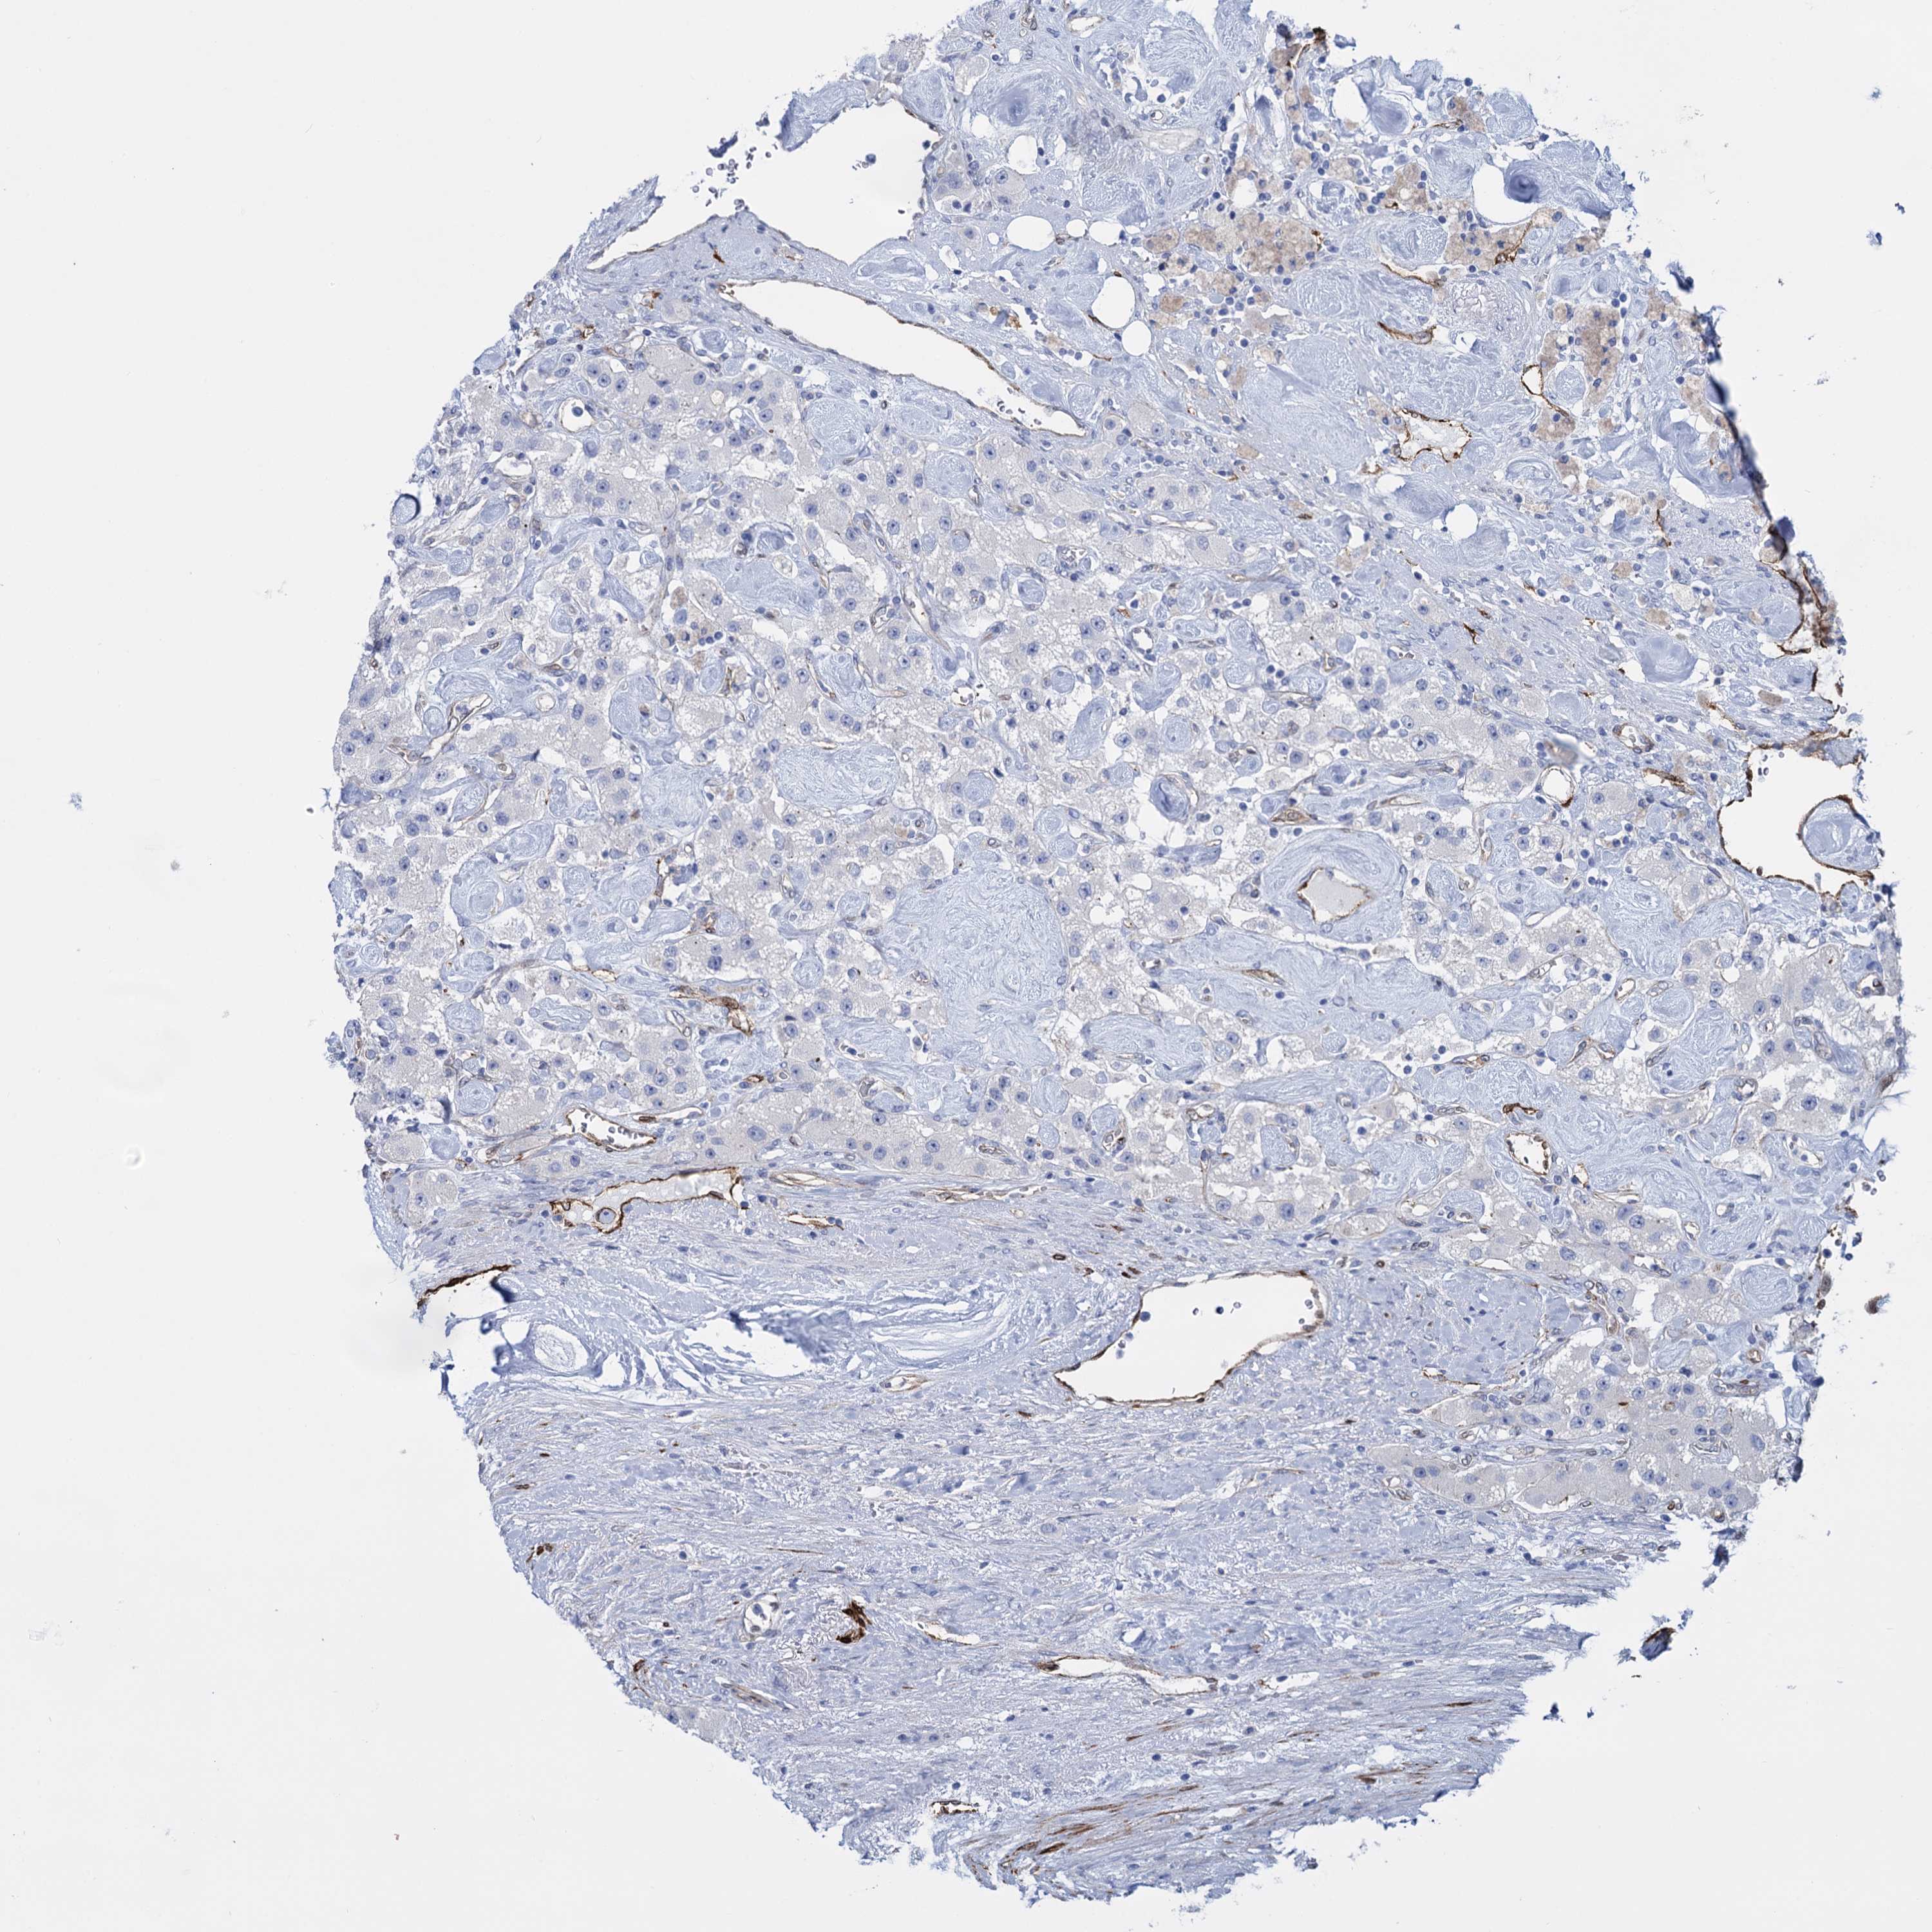

CARCINOID - Protein expressioni

A mouse-over function shows sample information and annotation data. Click on an image to view it in a full screen mode. Samples can be filtered based on level of antibody staining by selecting one or several of the following categories: high, medium, low and not detected. The assay and annotation is described here.

Antibody stainingi

Antibody staining in the annotated cell types in the current human tissue is reported as not detected, low, medium, or high, based on conventional immunohistochemistry profiling in selected tissues. This score is based on the combination of the staining intensity and fraction of stained cells.

Each image is clickable and will lead to virtual microscopy that enables deeper exploration of all samples and also displays staining intensity scores, fraction scores and subcellular localization as well as patient and tissue information for each sample.

Antibody HPA014404

Staining

High

Medium

Low

Not detected

Intensity

Strong

Moderate

Weak

Negative

Quantity

>75%

75%-25%

<25%

None

Location

Nuclear

Cytoplasmic/membranous

Cytoplasmic/membranous,nuclear

Carcinoid, malignant, NOS

Carcinoma, NOS